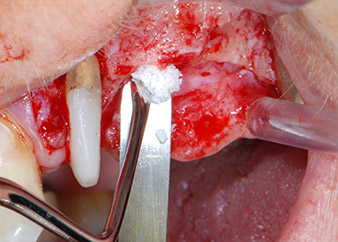

Vor der Insertion der Implantate und nach Überprüfung der intakten Schneiderschen Membran (Abb.9) wurde der interne Sinusboden an beiden Implantatpositionen mittels eines xenogenen Knochenersatzmaterials (Abb. 10) augmentiert.

Dann wurden die Implantate (Restore, Keystone Dental) mit dem Implantatmotor eingesetzt (Abb. 11 und 12).